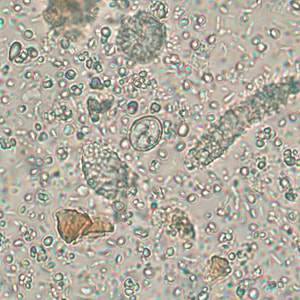

A 25-year-old refugee from Myanmar was screened for parasites at a local clinic in Tennessee. Stool specimens were collected in 10% formalin and polyvinyl alcohol (PVA) and sent to the state health laboratory for ova and parasite (O&P) work-up. Figures A–D show what was observed in a concentrated wet mount made from the formalin-preserved stool. Figures A and B show what was observed under brightfield microscopy; Figures C and D show the same fields, respectively, observed under UV microscopy. All images were captured at 400x magnification. The objects of interest measured on average 17 micrometers long by eight micrometers wide. What is your diagnosis? Based on what criteria?

Figure A